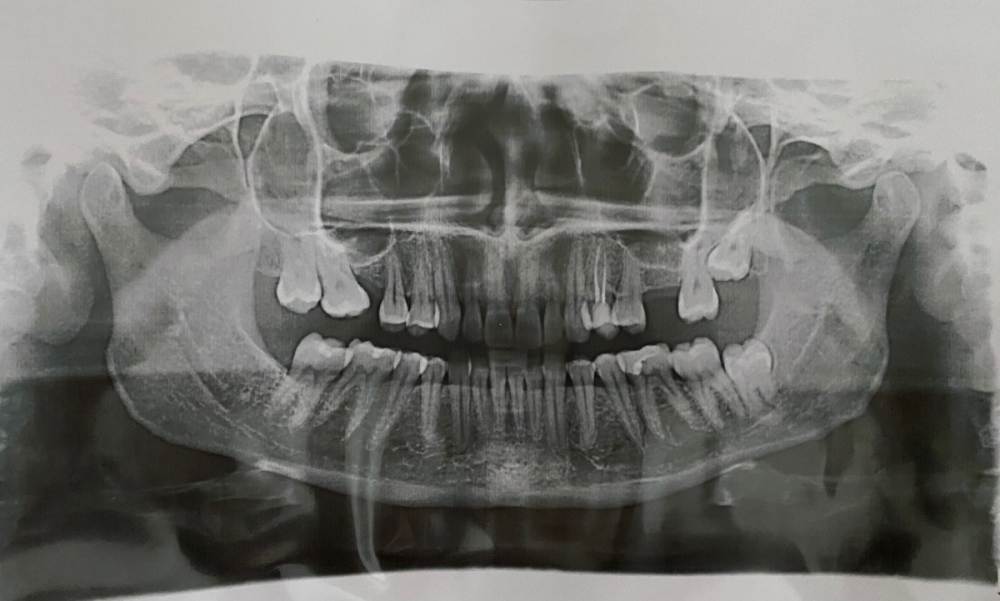

Подскажите, возможно ли перемещение верхних 8к на место 7к , а 7к на 6ки в моем случае? Я знаю, что это долго.

До пандемии я нашла двух врачей, которые уверенно сказали, что такое возможно. Далее, случилась пандемия и брекеты пришлось отложить) Придя недавно на консультацию мне вдруг оба заявили, что нет двигать не будет: долго, пазуха низко, вообще только имплант.

Еще меня беспокоит нижняя 8-ка, по кт в ее корнях проходит нерв, и как мне сказали, при удалении его повредят и будут разные последствия. Можно ли его оставить на месте?

FB5E8F99-7980-41FB-A154-EAF3E33FD2C0.jpeg